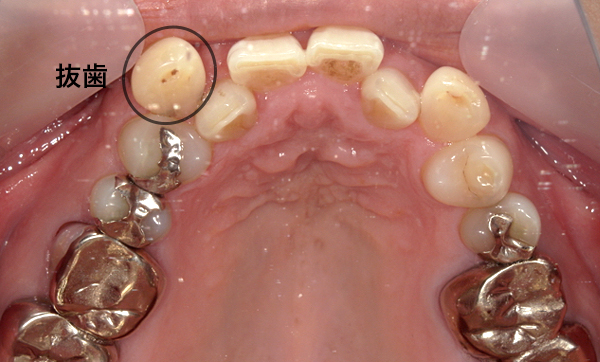

抜歯を伴った部分矯正の症例

当院は基本的には抜歯せずに、ディスキング(歯の横の面をエナメル質の範囲内で多少削る)にて歯列矯正しています。

ただし、部分矯正でも必要であれば抜歯を行なって治療を行うこともございます。

また、歯を並べるスペースが元々確保できる場合は、抜歯もディスキングも行わずに治療します。

| Before | After |

|---|---|

|

症例詳細:上顎の部分矯正、治療期間:7ヶ月、矯正装置1本:3.5万円+tax、リスク:後戻りの可能性